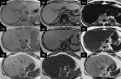

MRI is widely used in clinical practice for detecting liver diseases. Since the introduction of gadoxetic acid, MRI has become the most effective modality for the detection and characterization of focal liver lesions. According to previous meta-analyses, the area under the receiver operating characteristic curve (AUROC) was 0.97-0.99 for the diagnosis of small hepatocellular carcinoma (≥ 2 cm) by gadoxetic-acid-enhanced MRI. Moreover, the AUROC for the diagnosis of colorectal liver metastases was significantly high (0.98). Despite gadoxetic acid's drawbacks, its clinical utility outweighs them, making it the contrast agent of choice in routine liver MRIs. Moreover, clinically, liver MRI has become more prevalent for a quantitative assessment. Liver fibrosis can be evaluated using MR elastography; whereas, hepatic steatosis and iron overload can be evaluated using proton density fat fraction, with high accuracy and reproducibility. This article reviewed the usefulness of liver MRI, which can be a comprehensive imaging modality in clinical practice.